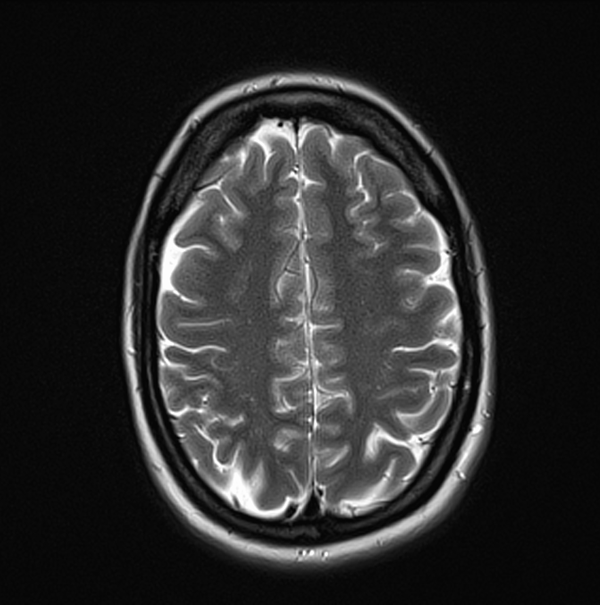

MRI Brain Anatomy 3T 3MM